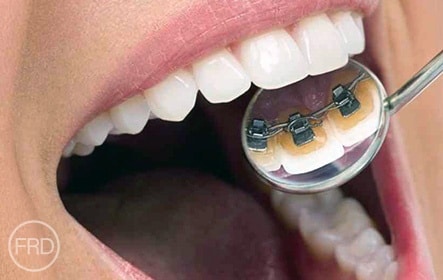

Lingual Braces

Lingual braces are placed on the inside (lingual side) of the teeth, making them virtually invisible from the outside. They provide the same effectiveness as traditional braces while remaining hidden from view. Since they are custom-made for each patient, they can take some time to adjust to but offer a great cosmetic solution for those who want discreet treatment.